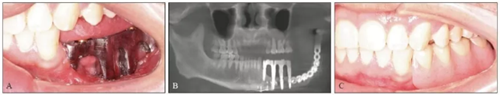

1.4.4 最終修復(fù)體戴入 最終修復(fù)體如圖14示。

卸下患者口內(nèi)的35~37臨時個性化復(fù)合基臺保護(hù)帽和34復(fù)合基臺保護(hù)帽,注射生理鹽水沖洗種植體及周圍軟組織,口內(nèi)試戴純鈦鑄造桿(圖15A),拍攝CBCT示鑄造桿與種植體復(fù)合基臺對接良好(圖15B)。將34~37膠托活動義齒就位于鑄造桿上部Locator附著體,囑患者做正中咬合及側(cè)方咬合,調(diào)磨咬合高點,拋光,完成最終修復(fù)體的戴入(圖15C、D)。囑修復(fù)后修復(fù)體及牙周維護(hù)。